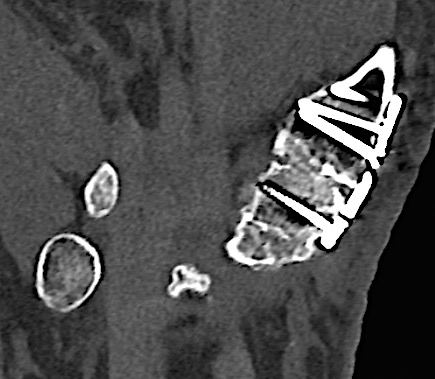

Case 1:

A 64-year-old male suffered a multi-fragmentary fracture of his right thumb metacarpal (Fig 1). An adapted 12-hole strut plate from the variable angle locking hand system was the implant of choice for fixation (Figs 2 - 4).

The strut plate provided good stability in a comminuted extraaricular fracture pattern and enables immediate mobilization. Bone callus formation was not witnessed during the healing process.